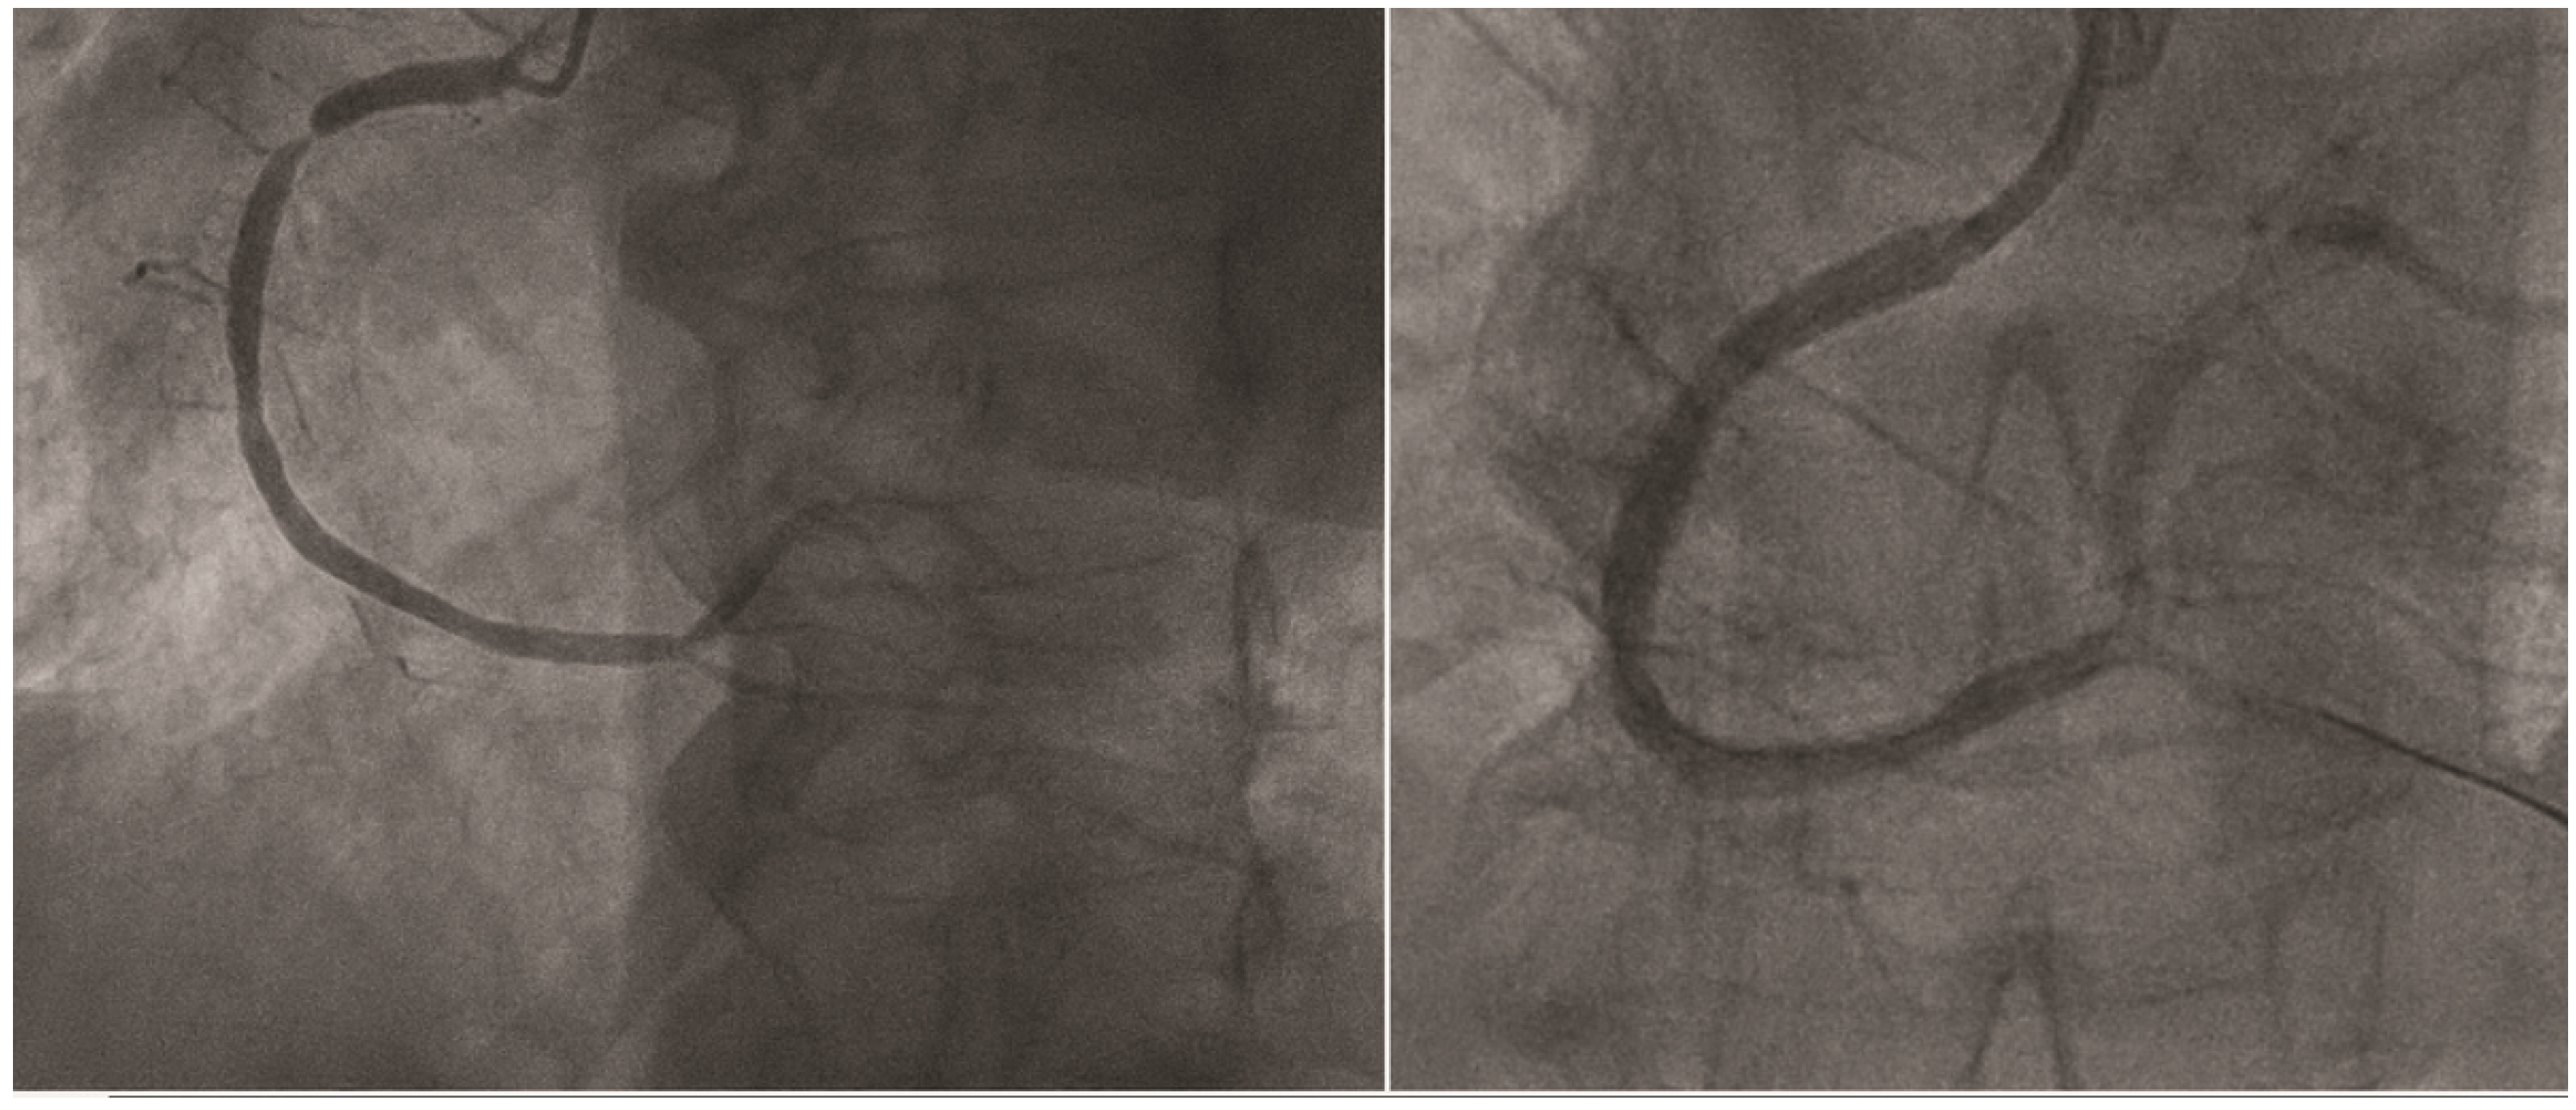

Impressive Late Stent Recoil of a Drug-Eluting Resorbable Magnesium Coronary Stent

Case description